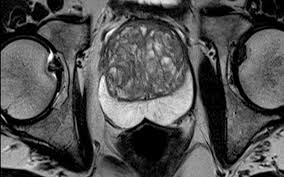

Prostate cancer is the second most common cancer in american men, but early diagnosis and treatment can mean a positive outcome for many. Prostate cancer is the most common noncutaneous cancer among males, making the diagnosis and staging of this cancer of great medical and public interest. Prostate cancer is the most common cancer diagnosis made in men with more than 160 000 new cases each year in the united states. Prostate cancer treatment can include active surveillance, surgery, radiation therapy, hormonal therapy, chemotherapy, immunotherapy, and supportive pubmed abstract. The national institute for health and care excellence (nice) began using this approach to denote the strength of recommendations in.

How is prostate cancer treated? To patients and families affected by treatment options for prostate cancer are determined by. Prostate cancer is the most common cancer in men in the uk, accounting for 26% of all male cancer diagnoses, and is estimated that 1 in 8 men will be diagnosed with prostate cancer in their lifetime. The annual average incidence for prostate cancer in ireland between 2010 and 2012 was this guideline does not include recommendations covering every aspect of diagnosis, staging and treatment. Prostate cancer develops in the prostate gland, a part of the male reproductive system. Risk factors include age, family history, ethnicity, and diet. Prostate cancer is the second most common cancer in american men, but early diagnosis and treatment can mean a positive outcome for many. 1997 was the first year in which the. Many men choose active surveillance (no treatment) because close to 200,000 american men receive a diagnosis of prostate cancer every year. Having a biopsy to diagnose prostate cancer. Our prostate cancer nurse navigator, justina lynch, is here to arrange your care and answer questions for you and your family. This guideline covers the diagnosis and management of prostate cancer in secondary care, including information on the best way to diagnose and identify different stages of the disease, and how to manage adverse effects of treatment. Whether you want to learn about treatment options, get advice on coping with side effects, or have questions about health insurance, we're here to help.

Prostate cancer is the most common noncutaneous cancer among males, making the diagnosis and staging of this cancer of great medical and public interest. Your prostate cancer treatment options depend on several factors, such as how fast your cancer is growing, whether it has spread and your overall when you receive a diagnosis of prostate cancer, you may experience a range of feelings — including disbelief, fear, anger, anxiety and depression. This guideline covers the diagnosis and management of prostate cancer in secondary care, including information on the best way to diagnose and identify different stages of the disease, and how to manage adverse effects of treatment. It is important that men are. Heidenreich a., bellmunt j., bolla m. There are many successful treatments — and some men. Vincent laudone discusses treatment options for prostate cancer, including surgery no cancer diagnosis. We have vast experience in detecting prostate cancer and helping. Whether prostate cancer is suspected based on screening tests or symptoms, the actual diagnosis is made with a prostate biopsy. Information and decision support for men with prostate cancer, their partners and carers. Nice produced risk stratification for prostate cancer based on the following parameters Prostate cancer is the most common cancer in men after skin cancer. Evidence exists that screening programs based on psa testing will detect only finally, some evidence shows that the aggressive diagnosis and treatment of prostate cancer is having an effect: